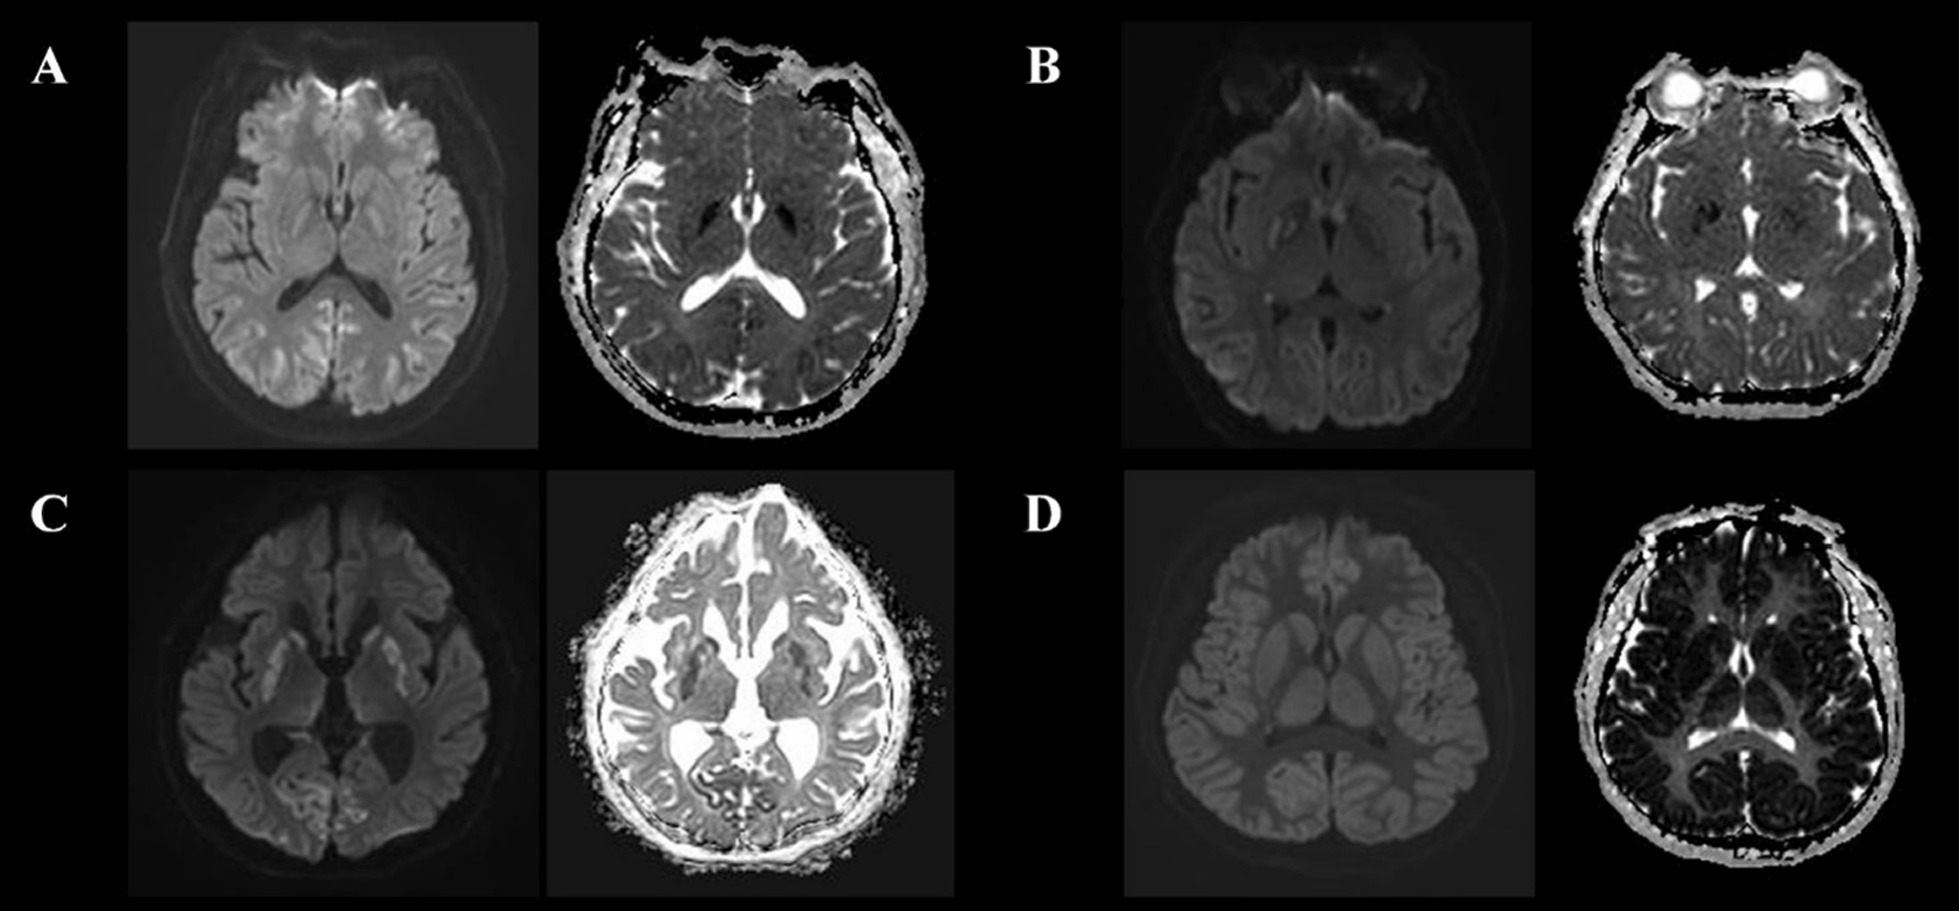

MRI scanning was performed using a 3 T scanner (Achieva, Philips Healthcare, Amsterdam, The Netherlands) and included DW-MRI, ADC measurements, and T2-weighted imaging. Forty consecutive DW-MRI sections per patient were acquired using standard b = 1000 s/mm2, and it was independently assessed by a neuroradiologist (I.H.L) and neurologist (H.S.J.) completely blinded to clinical information. PHSI was defined as a HSI on DW-MRI with corresponding hypoattenuation on the ADC map irrespective of volume after HIBI, and other cases as absence of HSI (AHSI) (Fig. 1) [20–22], and when there was a difference of opinion, it was resolved by consensus (see Additional file 1). However, patients with single or multiple HSI confined to a specific vascular territory on DW-MRI were excluded from this study because they were not presumed HIBI [23]. The % voxels of ADC threshold is defined as the PV below a different ADC threshold per total voxels, PV 650 was calculated as the percentage brain volume with voxels below 650 (< 650 × 10−6 mm2/s) ADC value. In addition, average ADC value is defined as the mean ADC of the entire brain. Lumbar catheter placement was performed using a Hermetic™ Lumbar Catheter Accessory Kit (Integra Neurosciences, Plainsboro, NJ, USA), and CSF samples and ICP were measured using a LiquoGuard® pump system (Möller-Medical, Fulda, Germany). To measure the NSE level, an electro-chemi-luminescence immunoassay kit (COBAS® e801, Roche Diagnostics, Rotkreuz, Switzerland) was used. To determine the extent of blood–brain barrier (BBB) disruption, we used an albumin quotient (QA) = albumin[CSF]/albumin[serum] value [24]. Brain non-contrast CT scans were obtained in 5-mm slices using a 64-channel system (Somatom Sensation 64, Siemens Healthineers, Munich, Germany), and a neuroradiologist (I.H.L) measured the Hounsfield units (HU) of the putamen (P), caudate nucleus (CN), posterior limb of the internal capsule (PIC), and corpus callosum (CC) to calculate the GWR ([P + CN]/[PIC + CC]).

Fig. 1.

Various pattern of ultra-early DW-MRI and ADC of OHCA survivals. A. A 70-years old male. Gyriform restrictive diffusion in occipital cortex. B. A 31-years old female. Gyriform and regional restrictive diffusion in occipital cortex, temporal cortex, and deep gray matter, respectively. C. A 74-years old male. Gyriform and regional restrictive diffusion in occipital cortex and deep gray matter, respectively. D. A 58-years old male. Extensive gyriform resticted diffusion in all gray matter. Abbreviations: OHCA, out-of-hospital cardiac arrest; DW-MRI, diffusion-weighted magnetic resonance imaging; ADC, Apparent diffusion coefficient